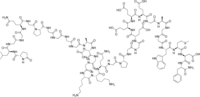

H-Pyr-Leu-Gly-Gly-Gln-Gly-Pro-Gly-Gly-Gly-Gly-Ala-Asp-Gly-Gly-Lys-Lys-Gln-Gly-Pro-Gly-Gly-Glu-Glu-Glu-Glu-Gly-Ala-Gly-Gly-Trp-Met-Asp-Phe-NH2 | |

L-pyroglutamyl-L-leucyl-glycyl-glycyl-L-glutaminyl-glycyl-L-prolyl-glycyl-glycyl-glycyl-glycyl-L-alanyl-L-alpha-aspartyl-glycyl-glycyl-L-lysyl-L-lysyl-L-glutaminyl-glycyl-L-prolyl-glycyl-glycyl-L-alpha-glutamyl-L-alpha-glutamyl-L-alpha-glutamyl-L-alpha-glutamyl-glycyl-L-alanyl-glycyl-glycyl-L-tryptophyl-L-methionyl-L-alpha-aspartyl-L-phenylalaninamide | |